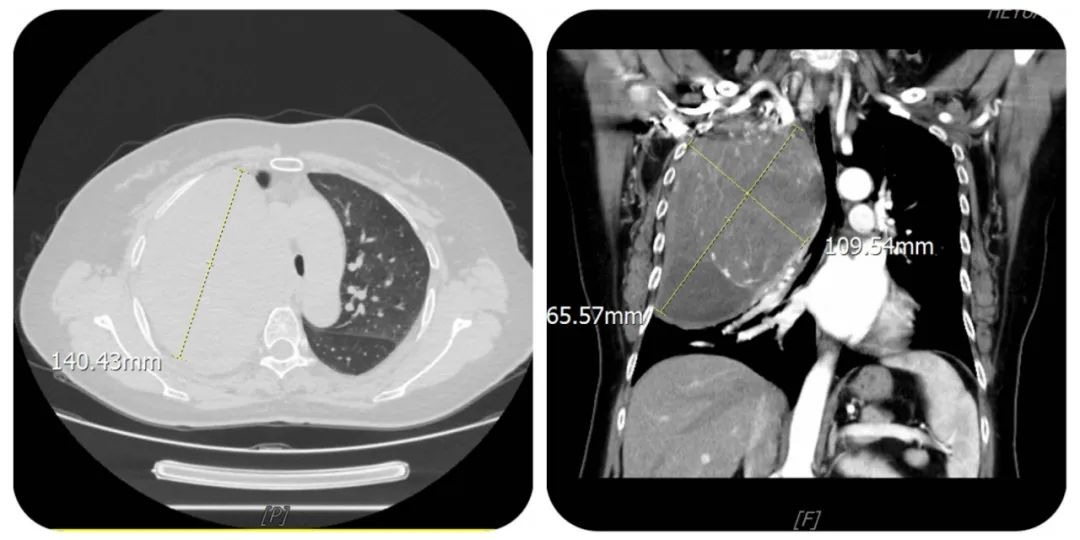

胸部增强CT检查是右上肺巨大肿瘤

入院后胸外科再次为患者进行了更详细的检查,增强CT结果显示这名患者的肺部不仅有这个巨大的肿瘤,而且已经出现了支气管狭窄、肺叶不张和胸腔积液等复杂情况,最关键的是需要立即确认这个巨大肿瘤是良性还是恶性的。为此,张主任专门组织了疑难病例讨论,大家一致认为患者右侧胸腔巨大占位,结合穿刺病理,考虑孤立性纤维肿瘤可能性大。但CT影像提示:动脉期可见病灶包绕右上肺动脉,胸膜增厚,不排除恶性肿瘤可能。如果是恶性肿瘤,可能因粘连严重导致胸壁甚至膈肌缺损大,应考虑胸壁、膈肌缺损修补问题,手术难度极大,和患者及家属充分沟通后,决定在全麻下行胸腔镜辅助小切口右上肺肿物切除术。

在胸腔镜的辅助下,张主任顺利分离了肿瘤与肺组织和胸壁的粘连,并完整切下了肿块,肿块约12cm大小,并最终判定为孤立性纤维性肿瘤,排除了恶性肿瘤的情况。